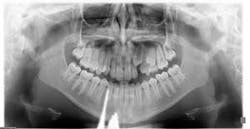

Before you begin treatment, take records. These include photos, x-rays, and diagnostic models. It is important to document the state of the patient prior to treatment. Regarding root resorption, it is essential to take radiographs. Any orthodontic treatment should include pretreatment and post-treatment radiographs that allow visualization of the roots. I recommend panoramic radiographs for this purpose. While it is common in general dentistry to take panoramic x-rays every five years, this is too long for patients in orthodontic treatment. Root resorption can be evident radiographically in as little as six months of orthodontic treatment. Because of this, I take panoramic x-rays every six to eight months in my practice.